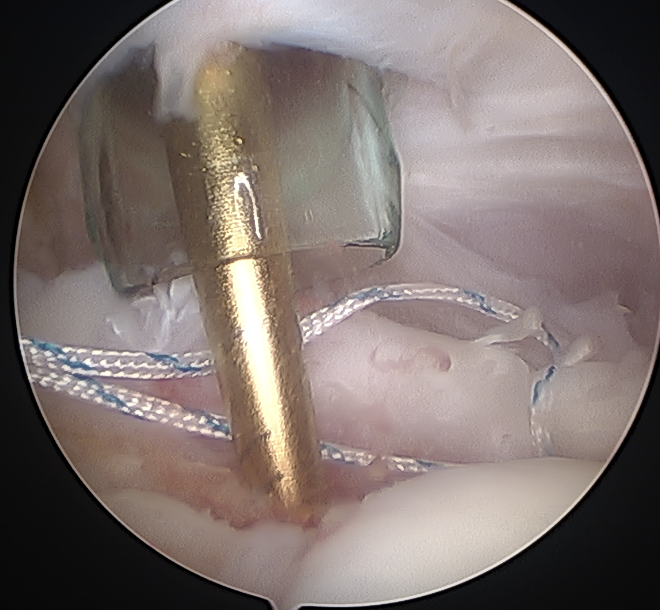

Portal just anterior to supraspinatus tendon

Tag biceps and release

Anchor biceps tendon into bicipital groove